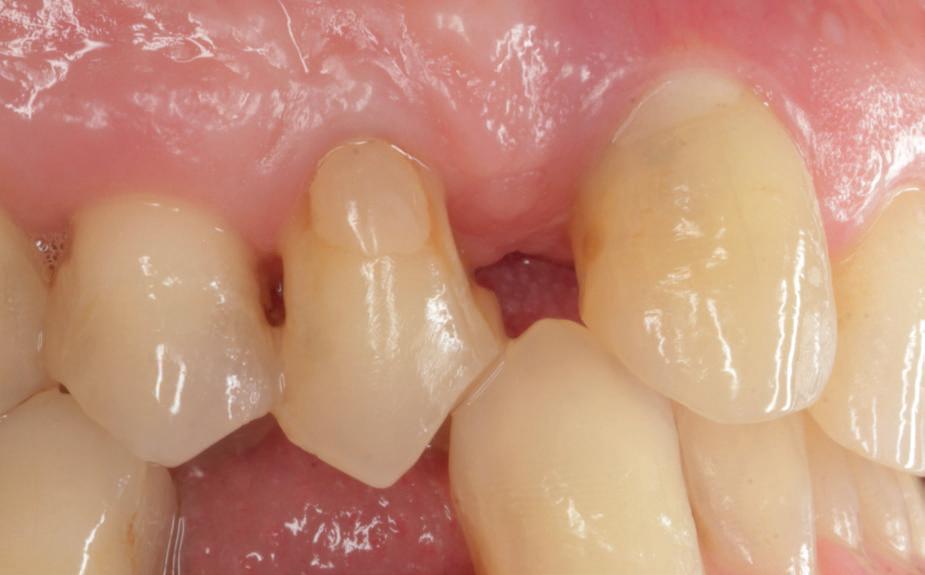

Eerst resto, dan endo!

Pas als het element een mooie coronale afsluiting, contactpunten en functionaliteit heeft, kan er overgegaan worden tot het uitvoeren van een endodontische behandeling. Zo kan er voorspelbaar gewerkt worden en kan het element een geruime tijd na de wortelkanaalbehandeling goed worden geëvalueerd.